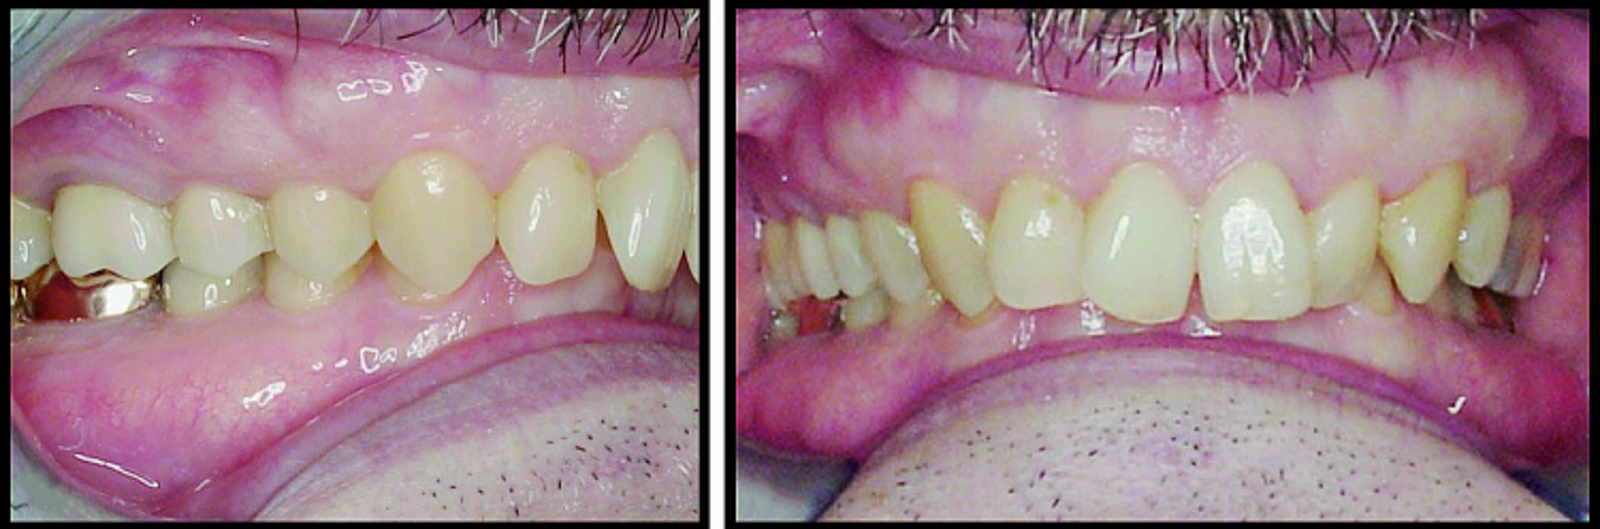

BiTurbo2 system for rapid deep overbite correction